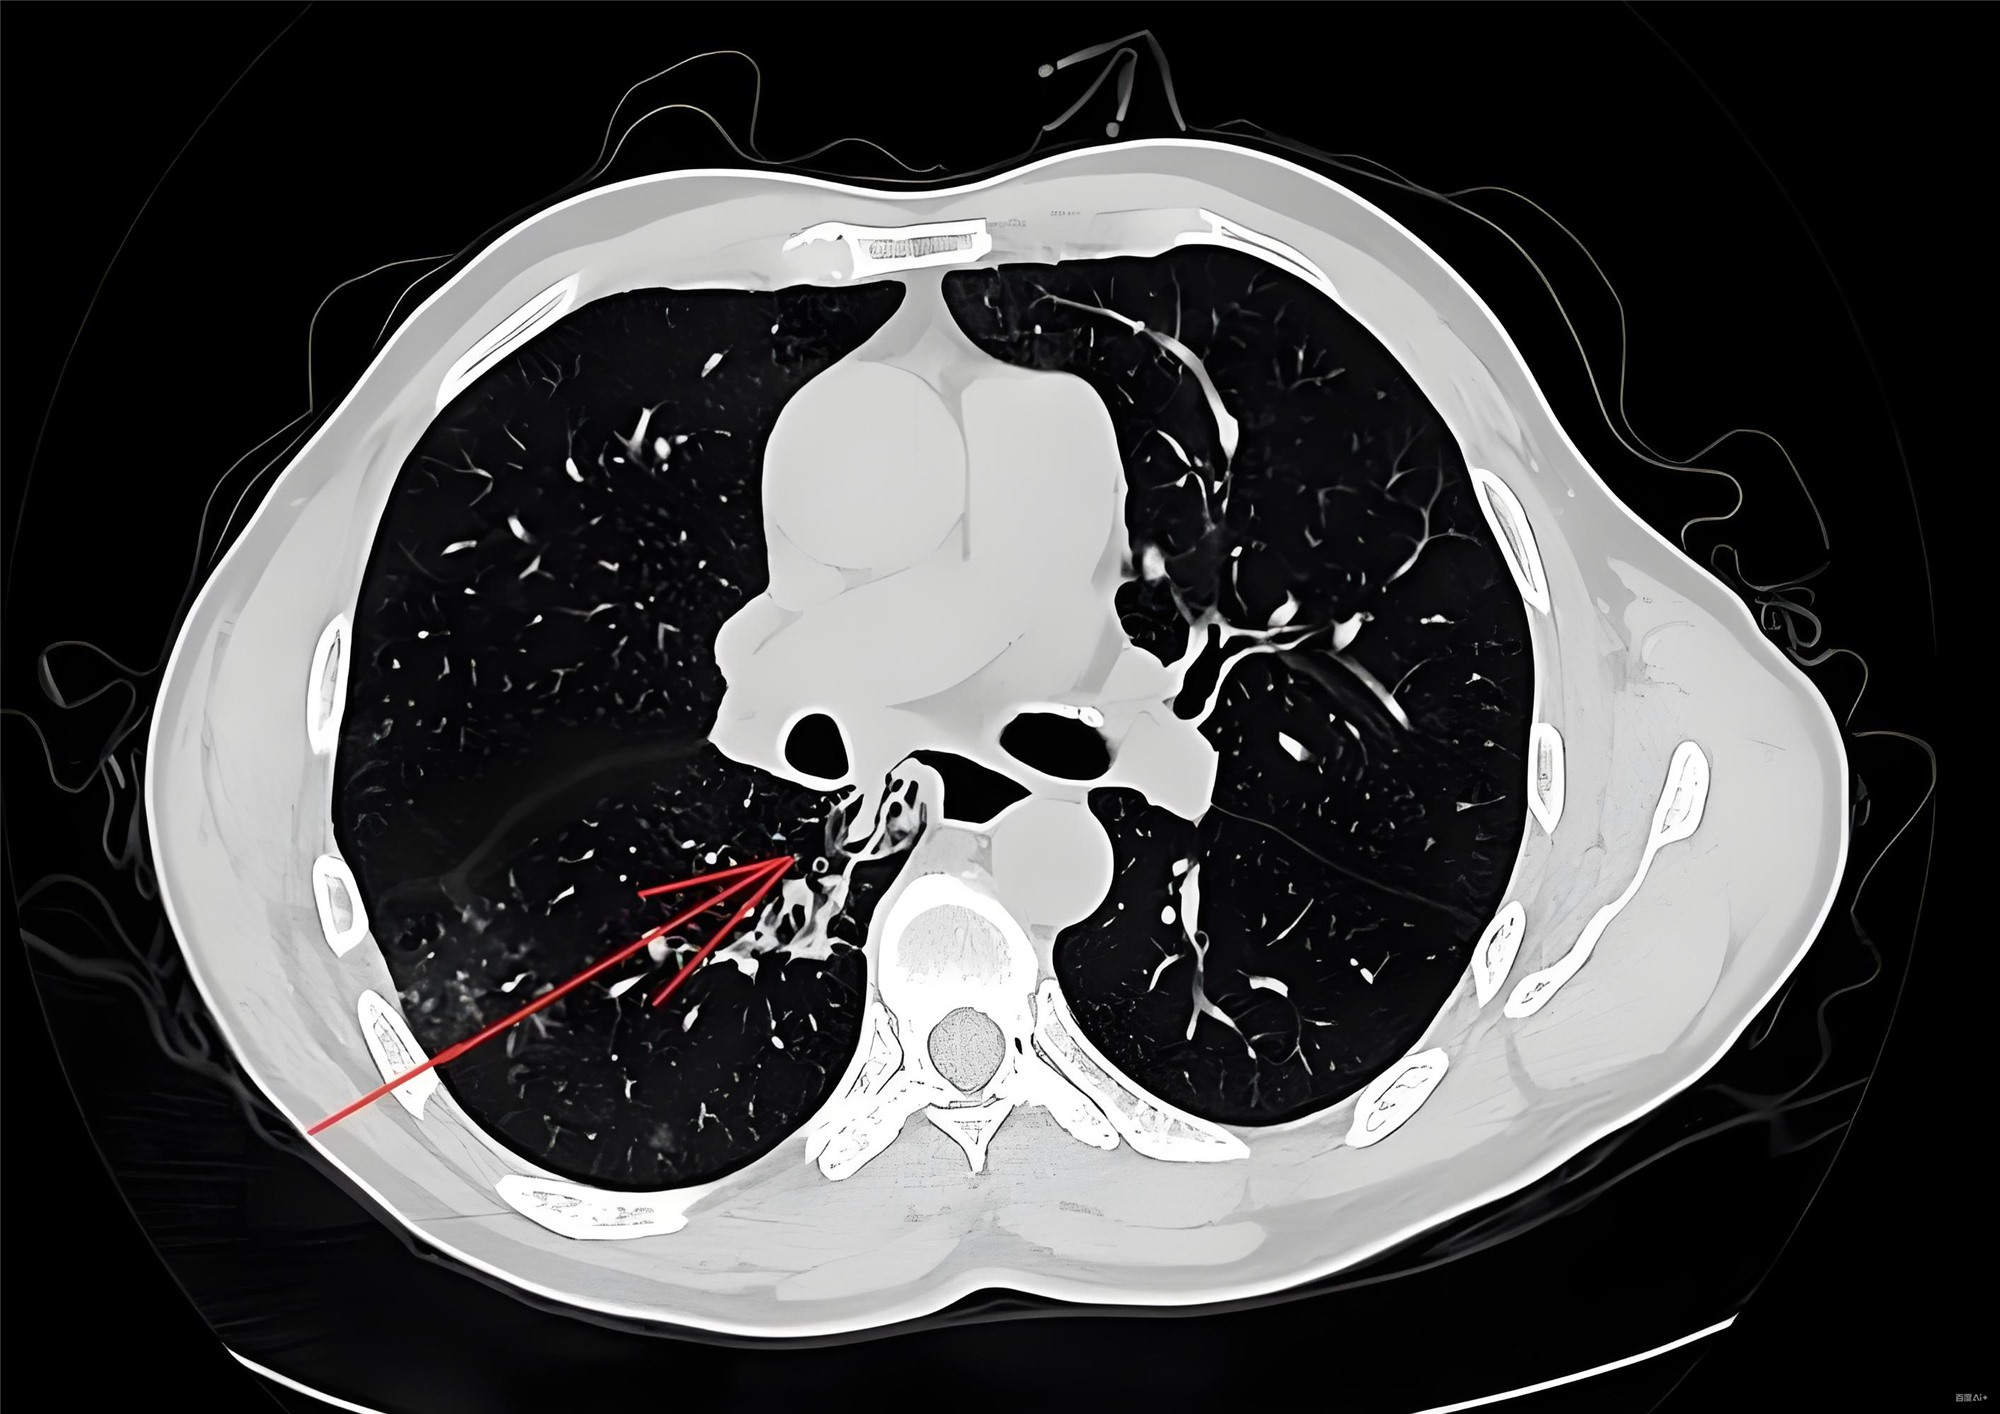

CTA确诊A型夹层